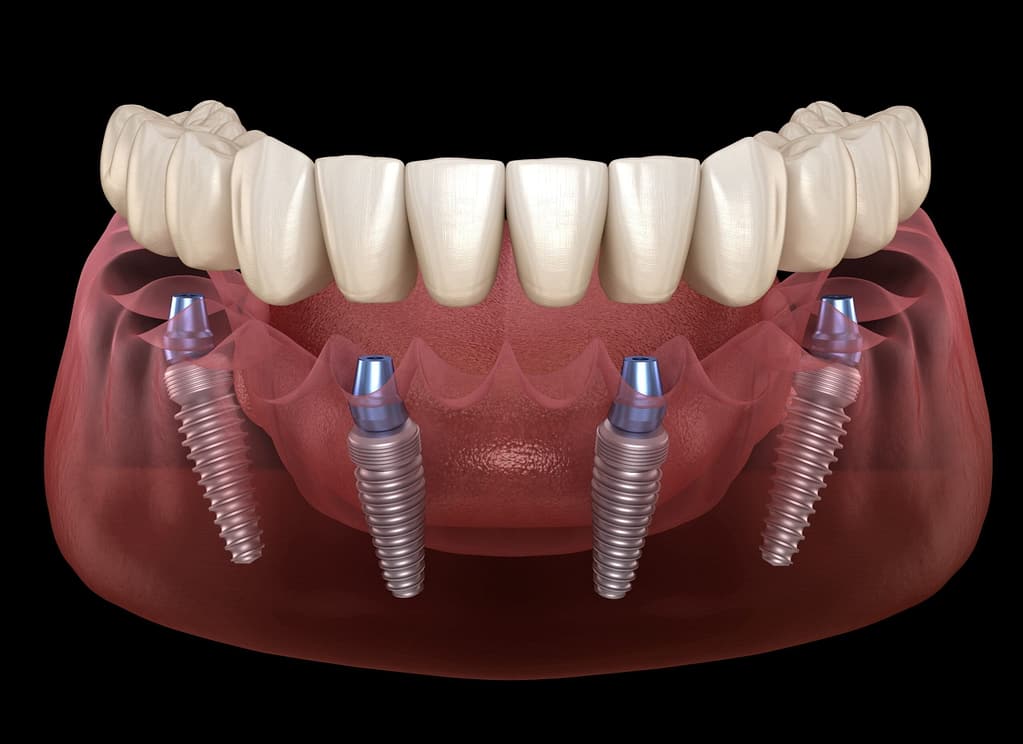

El All-on-4 (Todo sobre Cuatro) es un concepto quirúrgico y protésico desarrollado y patentado por el Dr. Paulo Maló, que se basa en la colocación estratégica de solo cuatro implantes dentales para soportar una prótesis fija completa e inmediata. La genialidad del concepto radica en la posición de esos cuatro implantes:

- Implantes Anteriores: Se colocan dos implantes rectos en la parte frontal de la mandíbula o el maxilar.

- Implantes Posteriores: Se colocan dos implantes en la zona posterior, pero con una inclinación de hasta 45 grados.

1.- Evitar el Hueso Deficiente: Esta inclinación nos permite esquivar estructuras anatómicas críticas (como el seno maxilar en el maxilar superior y el nervio dentario inferior en la mandíbula) que suelen tener hueso deficiente.

2.- Aprovechar Hueso de Calidad: Nos permite anclarnos en las zonas del maxilar donde el hueso es más denso y voluminoso.

3.- Carga Inmediata: La colocación inclinada y la distribución de los cuatro puntos de anclaje garantizan la estabilidad primaria necesaria para la Carga Inmediata (colocar la prótesis fija el mismo día).